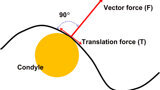

Fig. 9: The condyle position is based on the vector of force of the elevator muscles—perpendicular to the contour of the eminence.